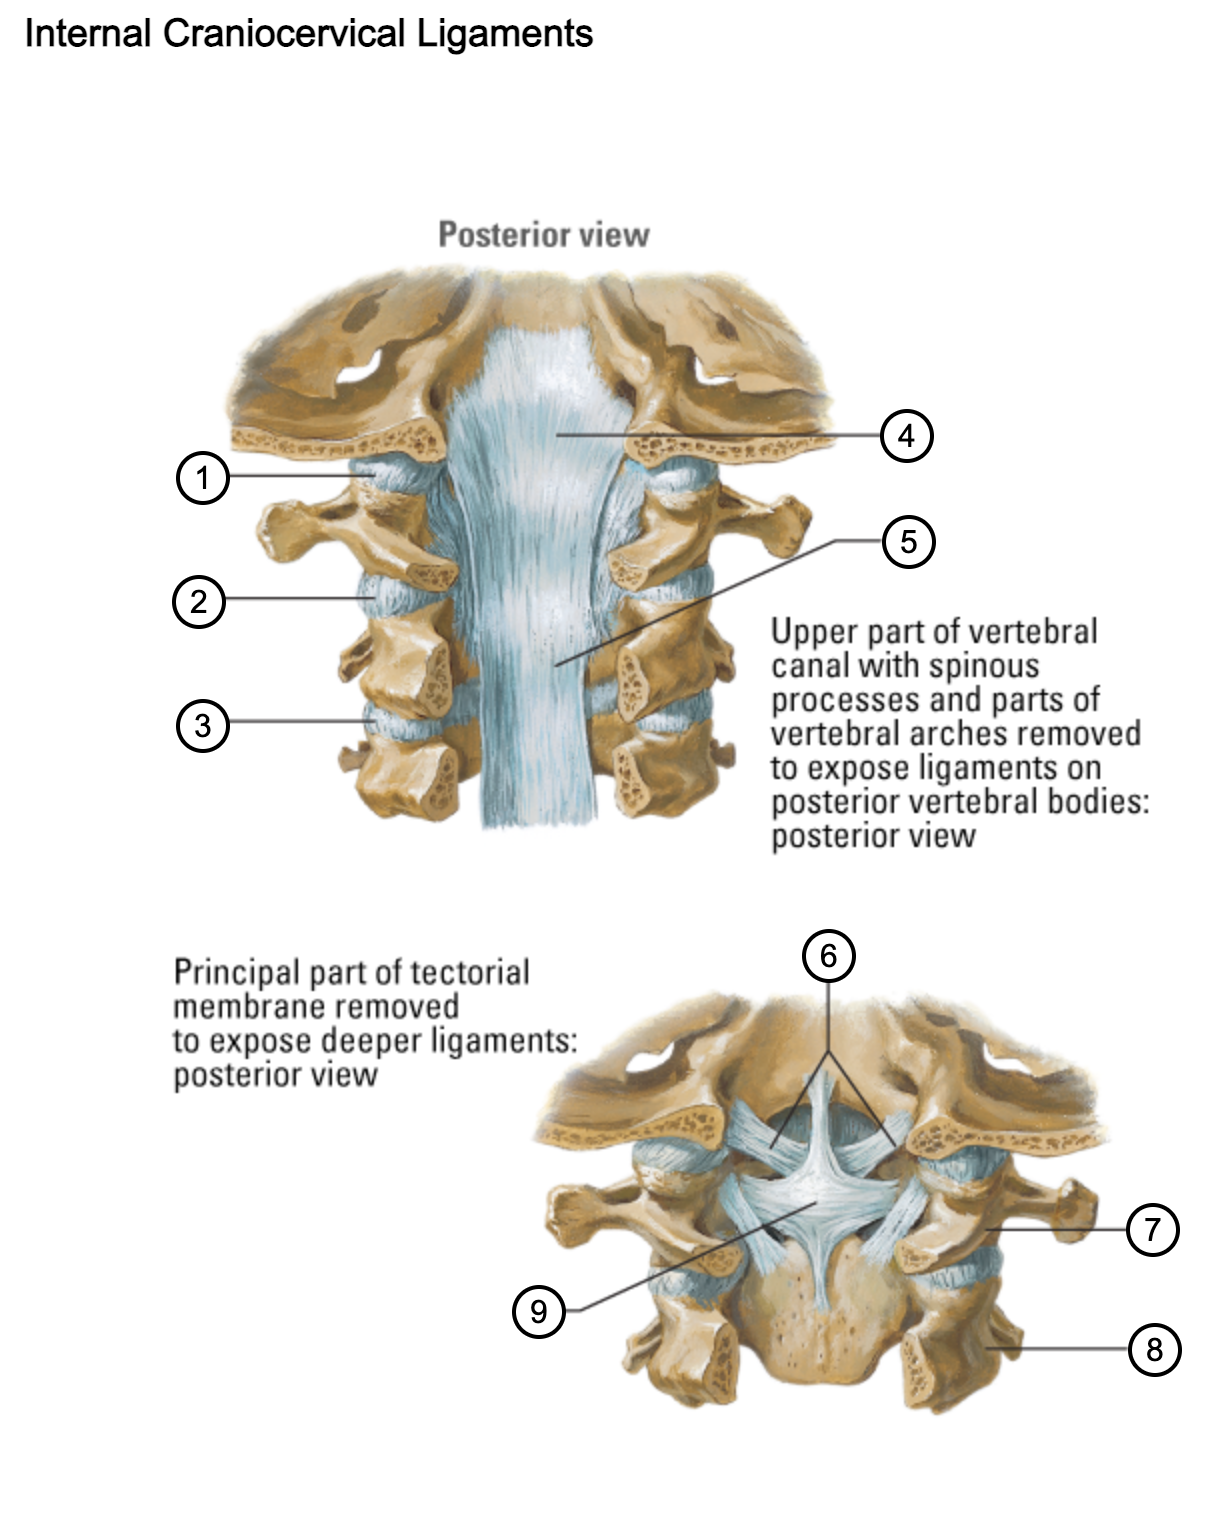

1

capsule of atlantooccipital joint

2

capsule of lateral atlantoaxial joint

3

capsule of zygapophysial joint (between axis and C3 vertebra)

4

tectorial membrane of cervical vertebral column

5

posterior longitudinal ligament

6

alar ligaments

7

atlas (C1)

8

axis (C2)

9

cruciform ligament (superior longitudinal band; transverse ligament of atlas; inferior longitudinal band)